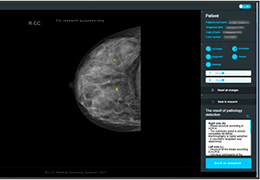

在这里,先进的智能功能自动执行手动任务和工作流程步骤,以简化流程,提高技术人员工作效率,节省时间和金钱,并增强患者护理。

自动化设备定位和患者姿势确认可优化放射科技师的效率并加快工作流程。

自动技术选择可改善影像一致性并支持辐射剂量控制。

这些功能利用数字控制面板分析运营、业务和临床绩效。

使管理员能够跟踪关键参数,包括平均曝光率、拒绝的影像和探测器统计信息。

帮助确定需要改进的方面,支持为员工和部门制定适当的改进计划。